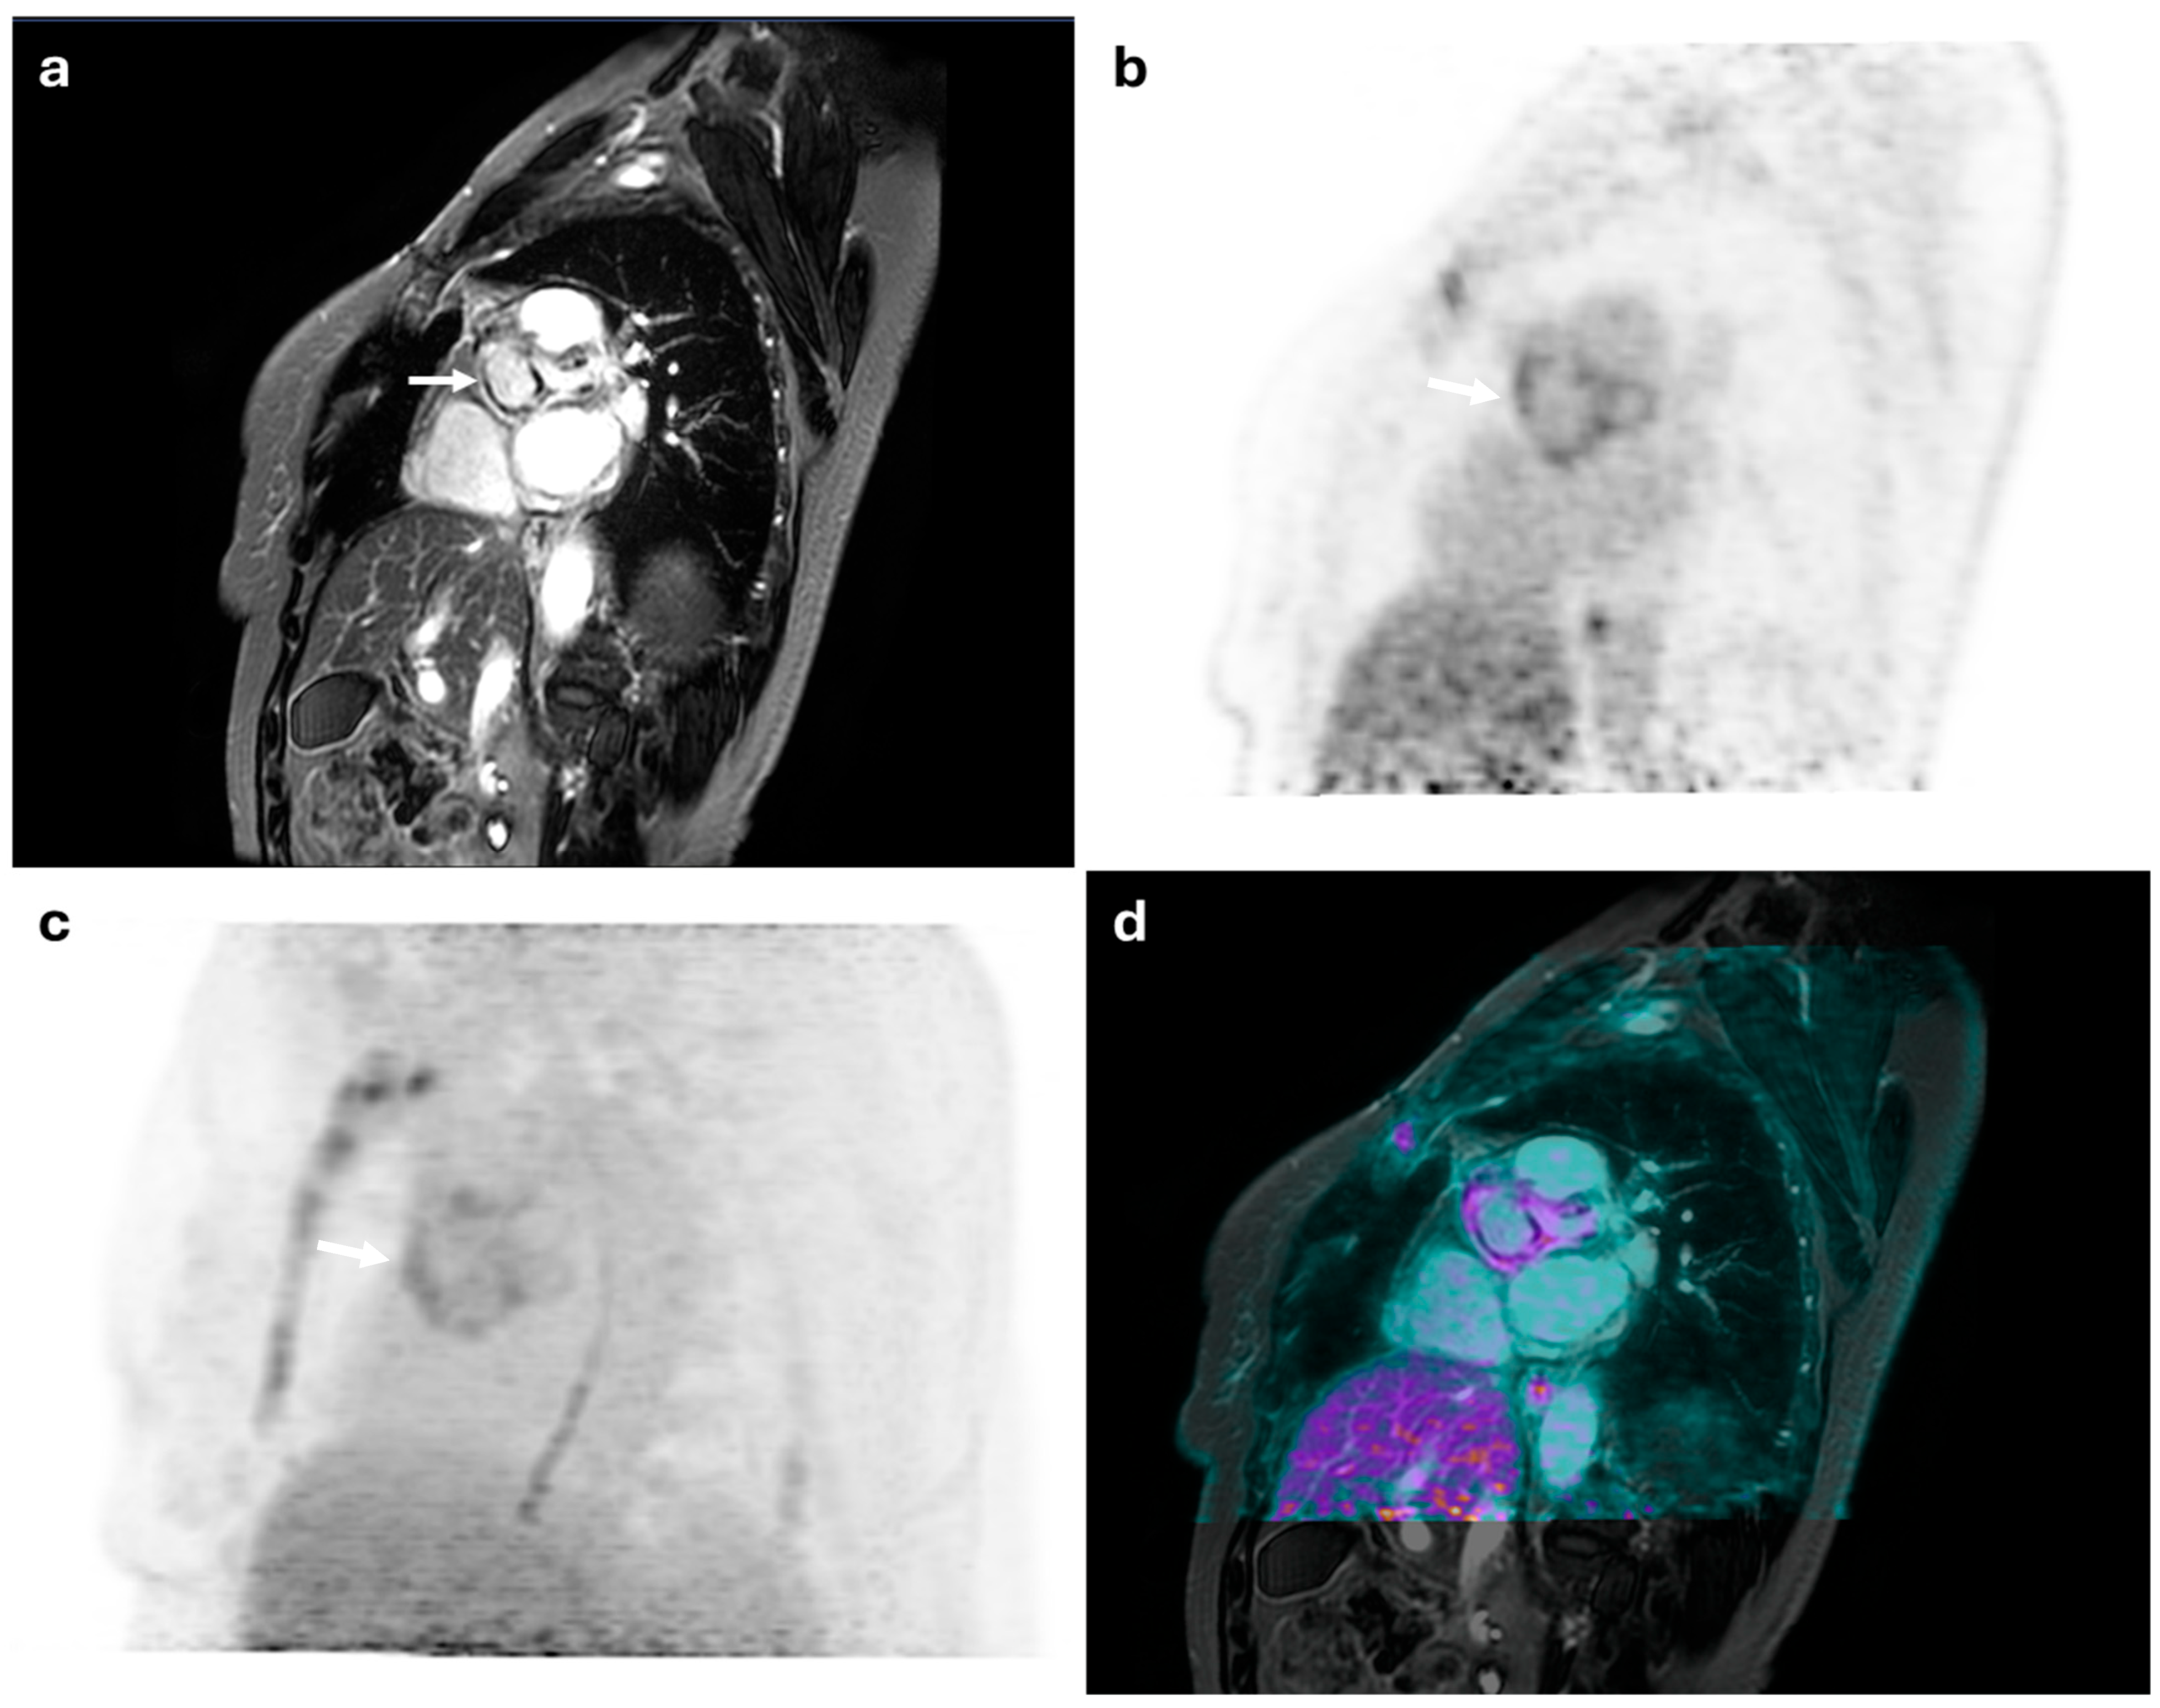

Figure 2.

52-year-old female with suspected aortic valve endocarditis. (a) shows a cardiac MRI image revealing thickening at the level of the aortic root in the paravalvular region, with extension into the ascending thoracic aorta. Late gadolinium enhancement highlights linear intramyocardial fibrosis in the paravalvular aortic area (white arrow). (b,c) display FDG-PET images demonstrating diffuse increased metabolic radiotracer uptake (SUVmax: 5 and 8) (white arrows). The combined PET/MRI findings were diagnostic of mitral valve endocarditis with extension to the sternum—predominantly the manubrium—and the adjacent retrosternal soft tissues at the same level (d).